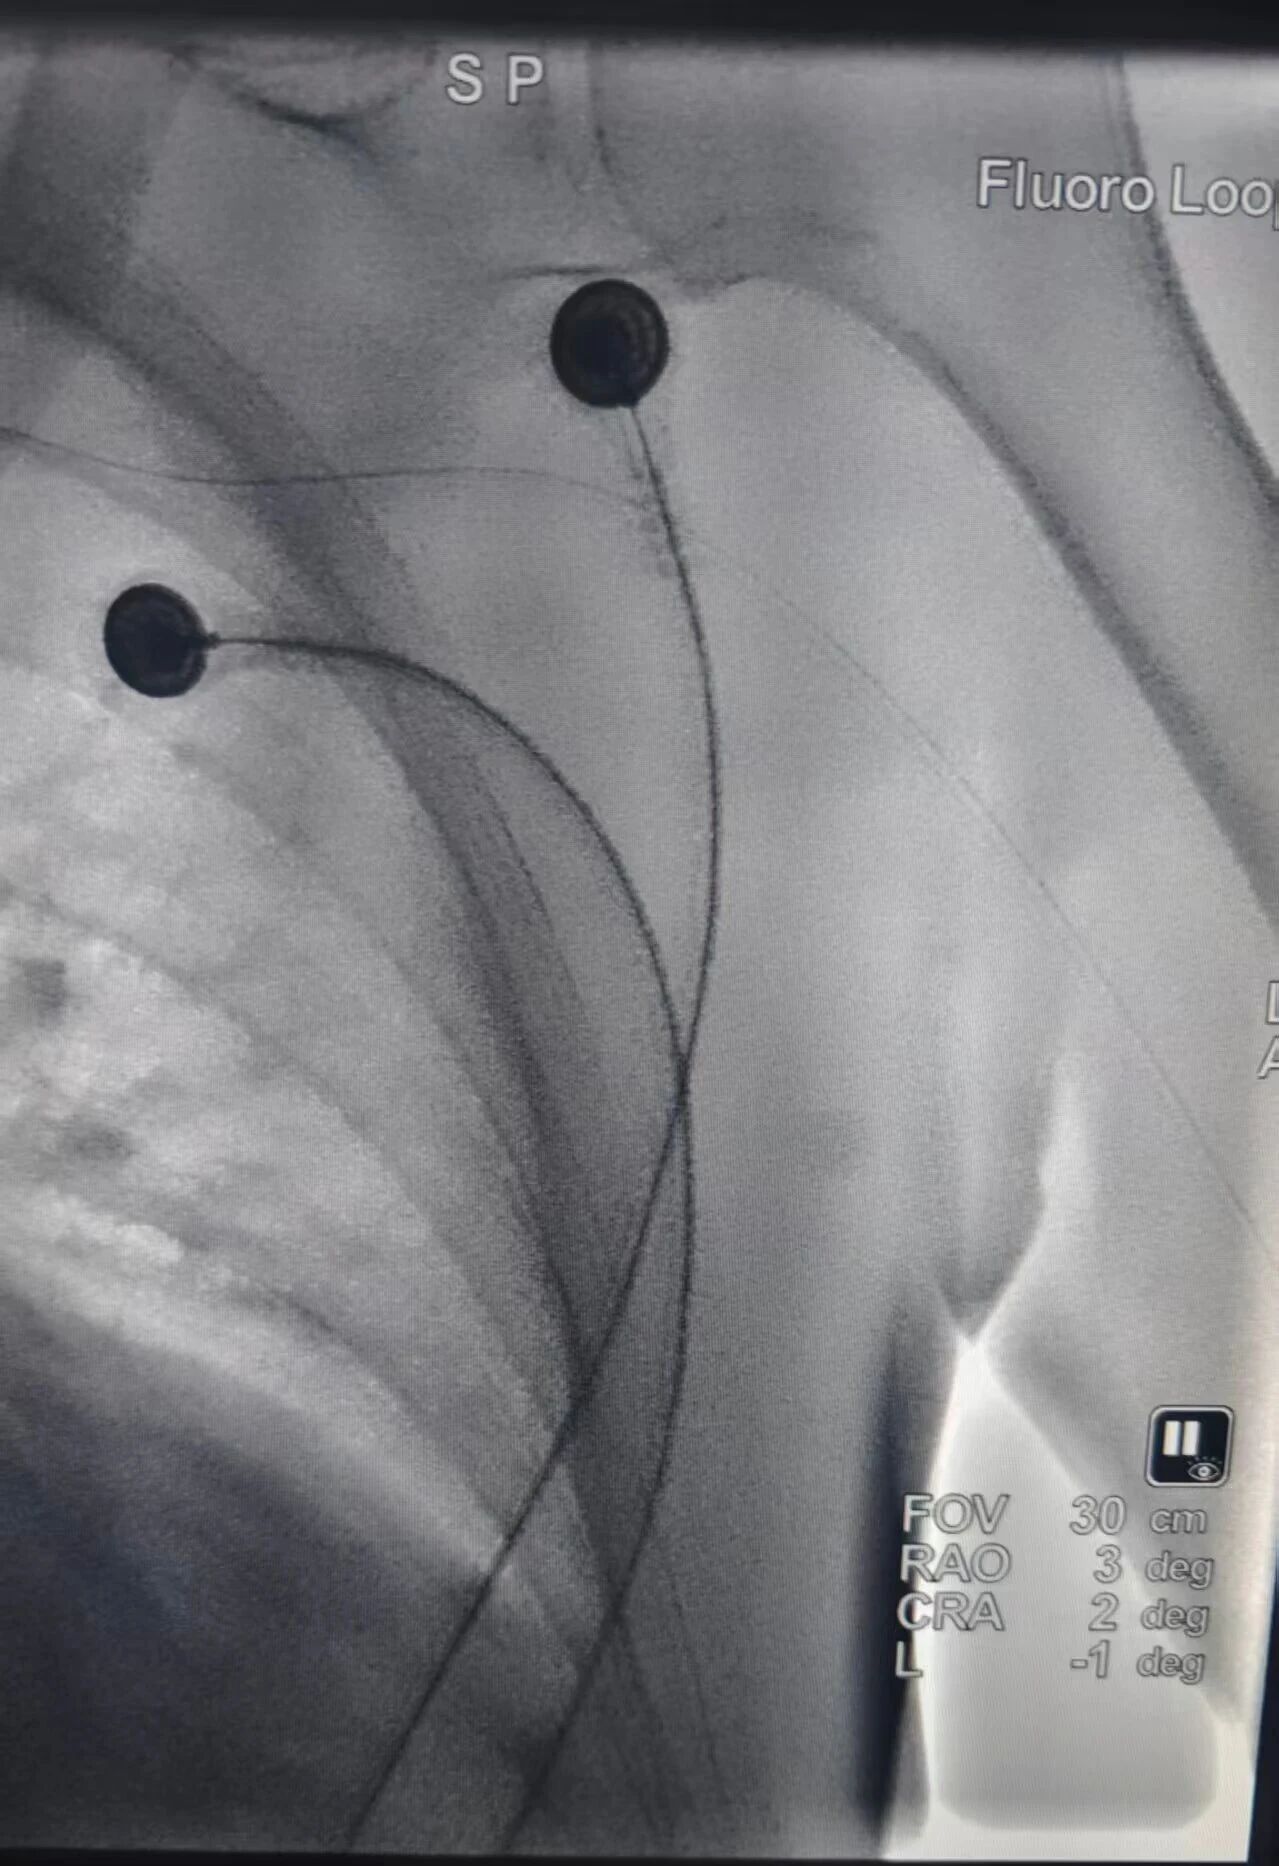

传统介入手术需要通过直径约2.1mm(5F)的血管鞘建立治疗通路,不仅穿刺创口相对较大,患者术后需卧床制动12—24小时,卧床周期长。而无鞘微导管技术彻底摆脱了传统血管鞘的“束缚”,医生以“穿针引线”般的精准操作,将直径仅0.5mm—0.86mm(1.9F-2.6F)的微导管借助导丝送入患者血管,最终精准抵达病灶位置。

这项技术的“极致微创”优势包括:穿刺入口直径不到0.9mm,和日常静脉输液的套管针大小相近,血管穿刺入口面积相比传统技术减少83%以上,大幅降低了血管损伤风险与术后并发症概率。手术多采用桡动脉(手腕)或肱动脉(肘部)等上肢入路,患者术后无需卧床。穿刺点仅需压迫止血2小时左右即可拆除绷带。不少患者术后能自行走下手术台,“走着回病房”已经成为常态,彻底打破了介入治疗“术后必卧床”的固有印象。极小的穿刺创伤让肱动脉具备极佳的可重复性,为需要多疗程治疗的患者搭建起了安全可持续的“生命通道”。